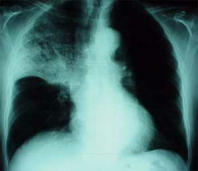

Blutgruppe AB hat - wie Blutgruppe A - ein chronisches Schleimproblem, das dauernd für Infektionskrankheiten anfällig macht: Nasennebenhöhlenentzünung, Bronchitis und Lungenentzündung (Pneumonie) etc.

Beispiel: Röntgenbild bei Oberlappen- pneumonie mit Verschattung im mittleren bis oberen Lungenbezirk rechts.

[3] Lungenentzündung (Pneumonie), Röntgenfoto: http://www.doktor.com/krankheiten/lungenentzuendung.html